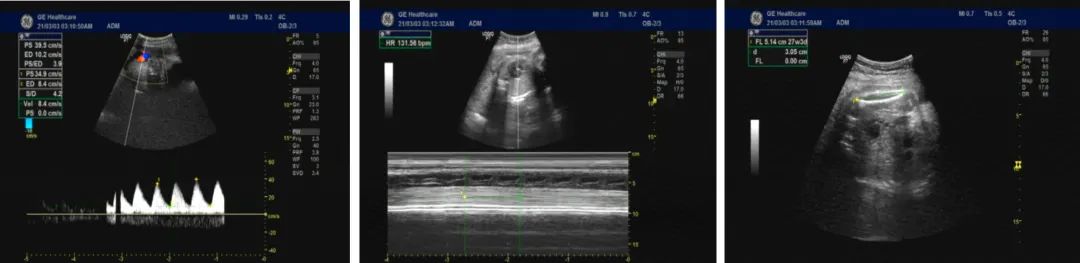

产科 B 超:胎盘厚度:47 mm;脐动脉:S / D:3.2~4.2。宫颈内口呈 Y 型,胎盘测径偏厚。脐动脉测值一过性增高。宫颈内口闭合不全。(图 1)

图1:产科超声,图片来源于作者

双顶径:74 mm,头围:269 mm;腹围:248 mm,股骨径51 mm;胎心率:140 次/分;

胎盘位置:右侧壁;成熟度:1-级;厚度:47 mm;胎盘下缘距宫颈:>20 mm;羊水指数:83;胎位:ROP;

脐带绕颈:一圈;

血流参数:脐动脉:S/D:3.2-4.2。宫颈内口呈“Y”型。

单活胎(头位),胎盘测径偏厚。

脐动脉测值一过性增高,宫颈内口闭合不全。